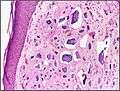

Micrograph of calcinosis cutis. The calcification is purple (bottom of image). H&E stain. | |